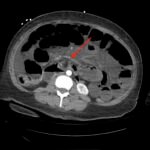

Recognition of the whirl sign on computed tomography (CT) imaging can improve patient outcomes in those presenting with small bowel obstruction (SBO). In the case highlighted in this report, a 40-year-old woman with a remote history of gastric bypass presented to the emergency department (ED) with four hours of abdominal pain and vomiting. Findings on the initial CT of the abdomen and pelvis were suggestive of SBO with a whirl sign pattern. The whirl sign occurs after the bowel rotates around the mesentery, leading to a visual “whirl” of mesenteric vessels. Unfortunately, despite prompt diagnosis, the patient developed an ischemic bowel and ultimately sustained a prolonged hospital course requiring multiple bowel resections. ED providers should familiarize themselves with the whirl sign because its presence in patients with SBO increases the likelihood of ischemia. These patients should have urgent surgical consultation to decrease overall morbidity and mortality.

Whirl sign, small bowel obstruction, gastric bypass, internal hernia.